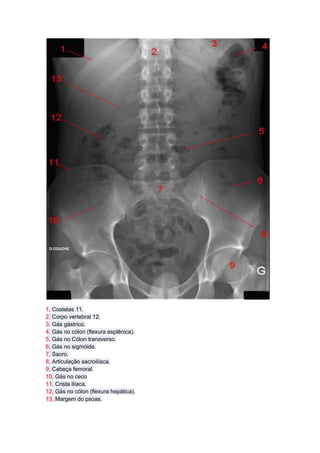

1, Costelas 11.

2, Corpo vertebral 12.

3, Gás gástrico.

4, Gás no cólon (flexura esplênica).

5, Gás no Cólon transverso.

6, Gás no sigmóide.

7, Sacro.

8, Articulação sacroilíaca.

9, Cabeça femoral.

10, Gás no ceco

11, Crista ilíaca.

12, Gás no cólon (flexura hepática).

13, Margem do psoas.

1, Costelas 11. 2,Corpo vertebral 12. 3, Gás gástrico. 4, Gás no cólon (flexura esplênica). 5, Gás no Cólon transverso. 6, Gás no sigmóide. 7, Sacro. 8, Articulação sacroilíaca. 9, Cabeça femoral. 10, Gás no ceco 11, Crista ilíaca. 12, Gás no cólon (flexura hepática). 13, Margem do psoas.